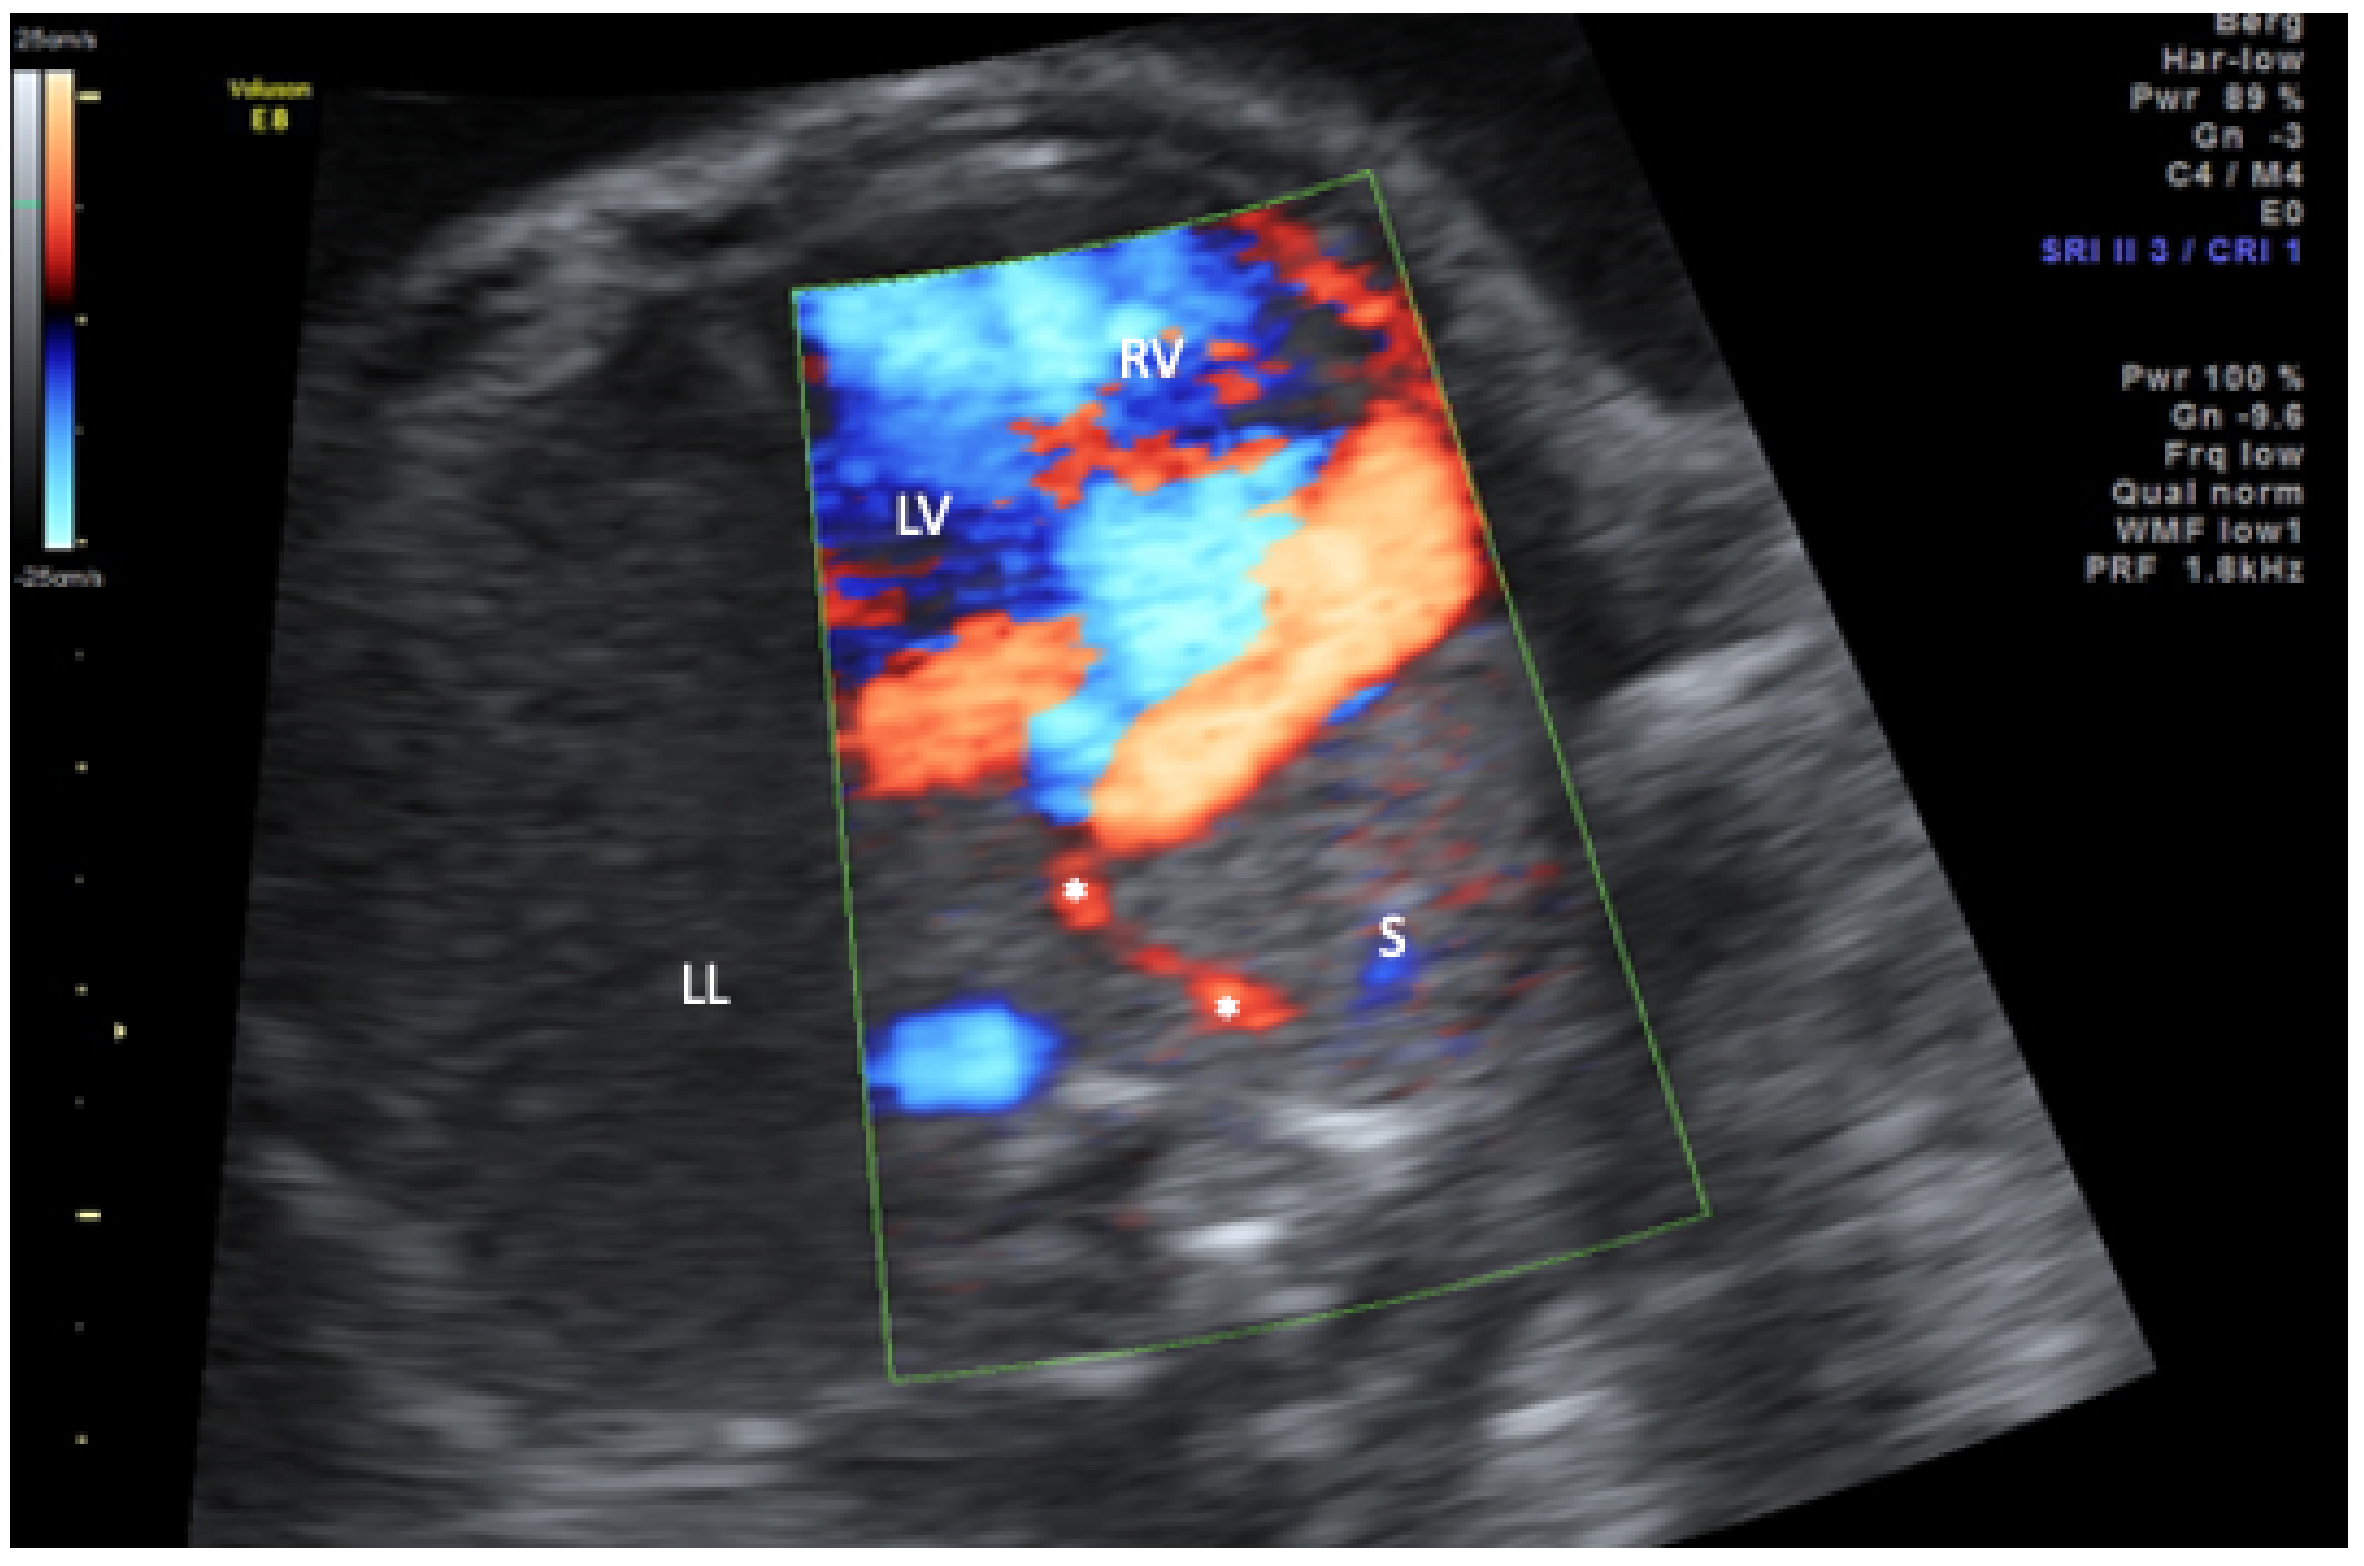

- Michailidis, G.D.; Simpson, J.M.; Tulloh, R.M.; Economides, D.L. Retrospective Prenatal Diagnosis of Scimitar Syndrome Aided by Three-Dimensional Power Doppler Imaging. Ultrasound Obstet. Gynecol. Off. J. Int. Soc. Ultrasound Obstet. Gynecol. 2001, 17, 449–452. [Google Scholar] [CrossRef]